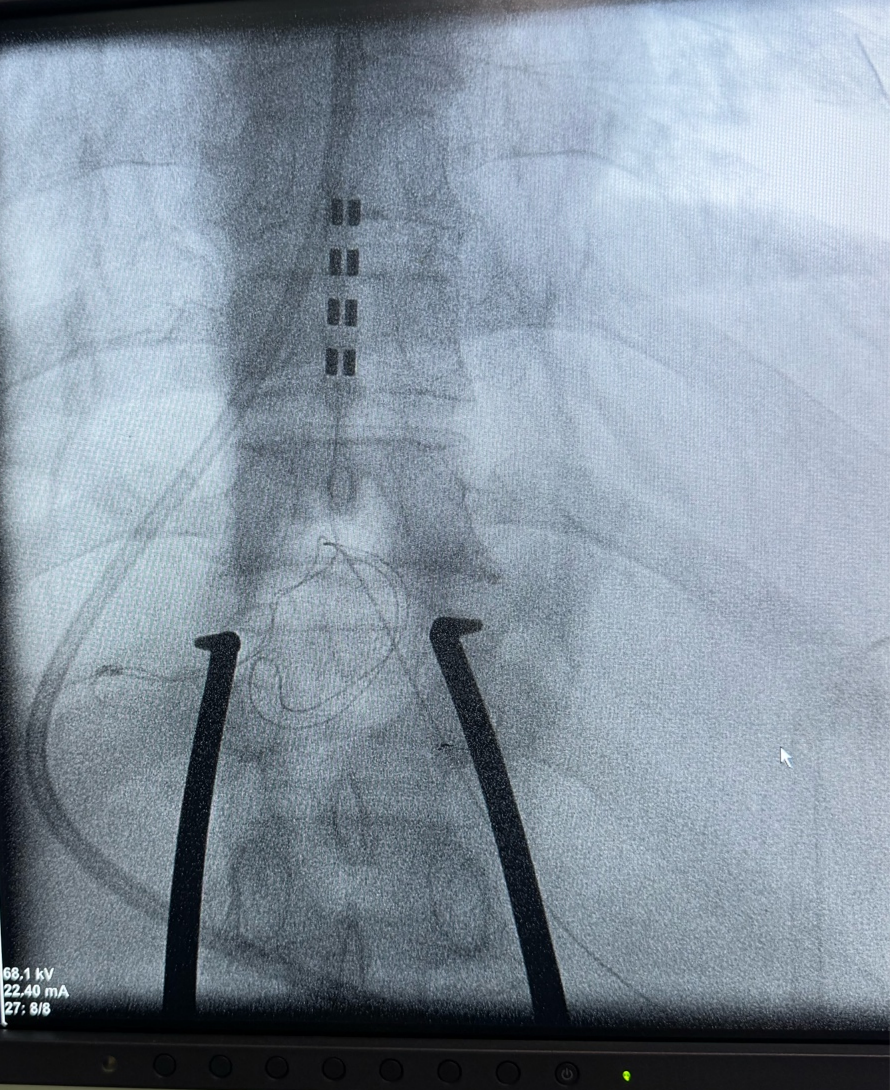

手术由龙乾发教授带领团队开展,将12*4排列的外科电极植入到脊髓硬膜外腔C3-5节段,12*4排列的外科电极植入到脊髓硬膜外腔T9-10节段,以同时起到促醒和缓解四肢肌张力高的作用。手术顺利,由于患者在颅脑创伤后身体机能受影响较大,术后恢复过程需谨慎监测,待患者生命体征平稳后开机调试刺激参数。期待患者能在SCS的助力下,逐渐恢复意识,重新回归正常生活。